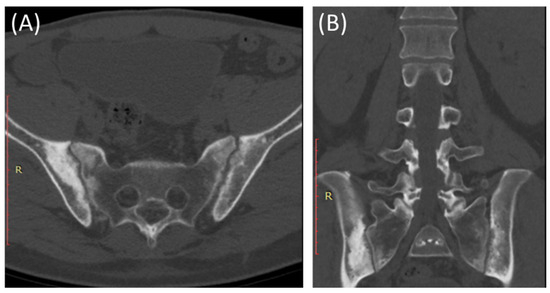

CT scans provide more detailed images of the sacroiliac joint and can reveal erosions, sclerosis, and joint space narrowing with greater clarity than X-rays [13]. Severe sacroiliitis, particularly in cases of ankylosing spondylitis, can lead to complete fusion or ankylosis of the sacroiliac joint [4]. CT scans can demonstrate the fusion as a solid, bony bridge between the sacrum and ilium [4]. CT scans can also assess soft tissues surrounding the SIJ, such as ligaments, tendons, and muscles, which may be inflamed in cases of sacroiliitis [44] as demonstrated in Figure 4 and Figure 5.

Figure 4.

Axial bone window CT scan (A) and coronal bone window CT scan (B) for a 41-year-old male presenting with Rt sciatica suggestive of bilateral sacroiliitis (same Patient as in Figure 3).

Figure 5.

Axial bone window CT scan (A) showing Chronic sacroiliitis with ankyloses of the sacroiliac and a sagittal bone window CT scan (B) showing Syndesmophytes in the spine in a 55-year-old patient with Ankylosing spondylitis.